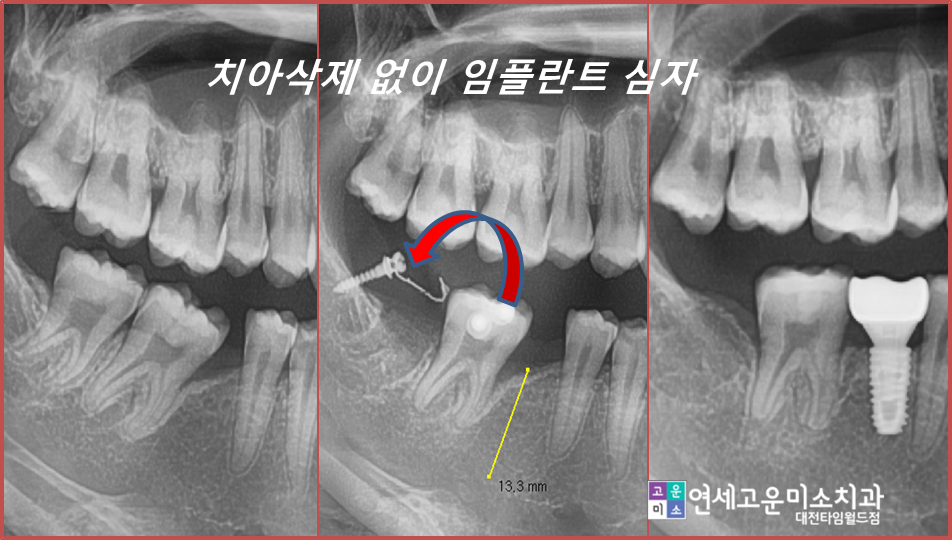

일련의 치료 과정입니다

이런 경우 간단한 부분교정을 통해서

쓰러진 치아를 세우고

공간을 확보한 후

임플란트를 심을 수 있습니다.

전혀 보이지도 않고 기간도 오래 걸리지 않습니다.

쓰러진 치아도 세워졌고

임플란트도 옆의 치아들 뿌리와 평행하게

심을 수 있게 되어 저작에도 유리한 상황입니다.